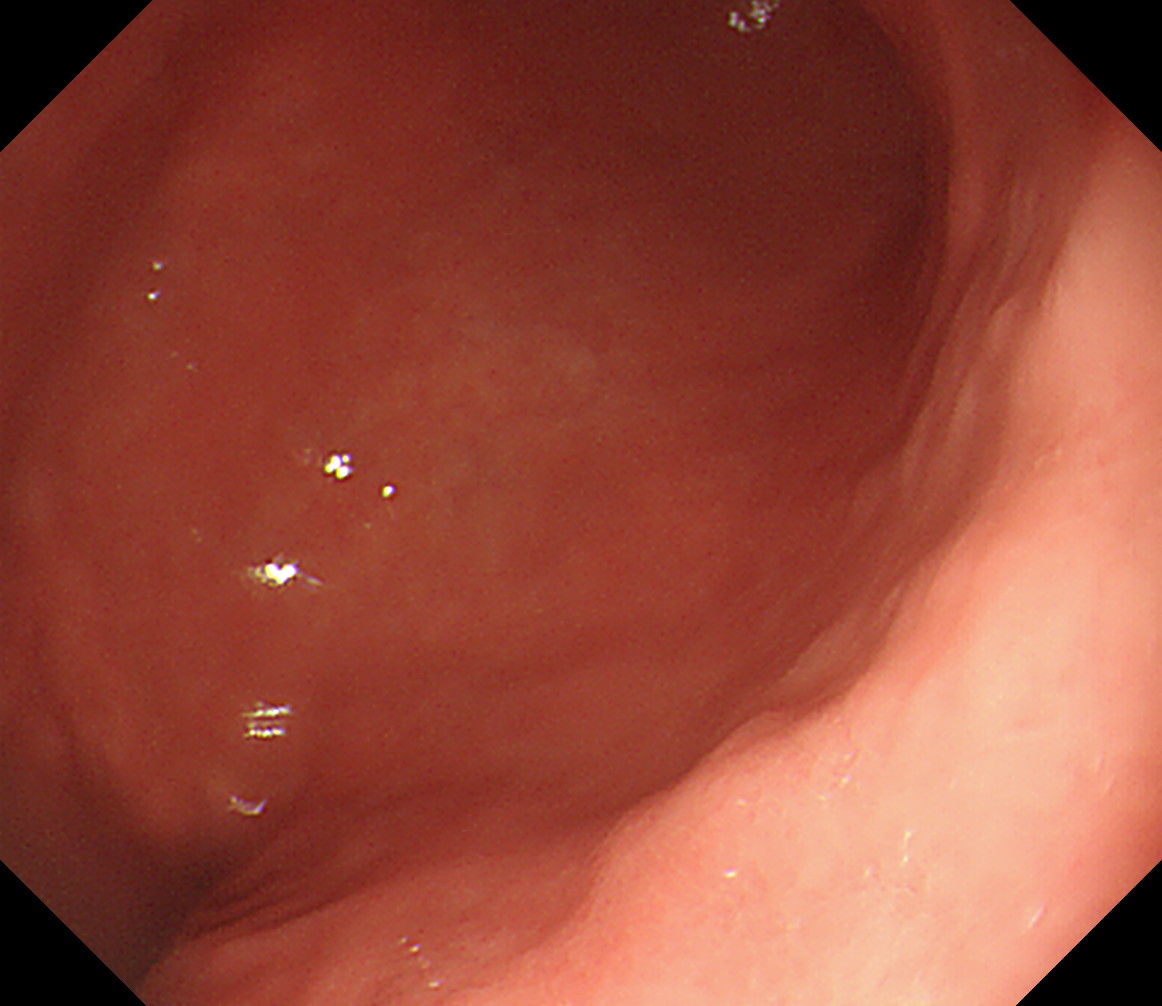

8 幽門輪 いわゆる「PーRing」 幽門輪

9 十二指腸球部前壁 十二指腸球部前壁

10 十二指腸球部後壁 この後十二指腸下降脚とVater乳頭を観察します 中部食道